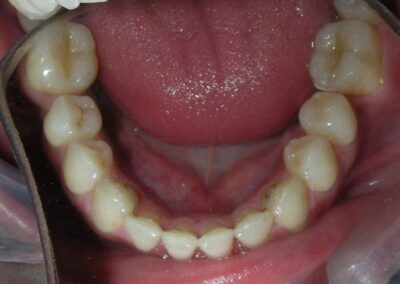

Intraoral Examination:

Absent #16, #36 and #46 , No Angle molar relationship . Projection of canines axes in class II relationship . Anterior open bite: Over Bite – 8 mm). Bilateral posterior crossbite: Involvement of upper posterior sectors with inverted buccal-lingual relationship. Moderate Crowding at the level of the upper and lower incisors. Acceptable Oral Hygiene with no periodontal issues